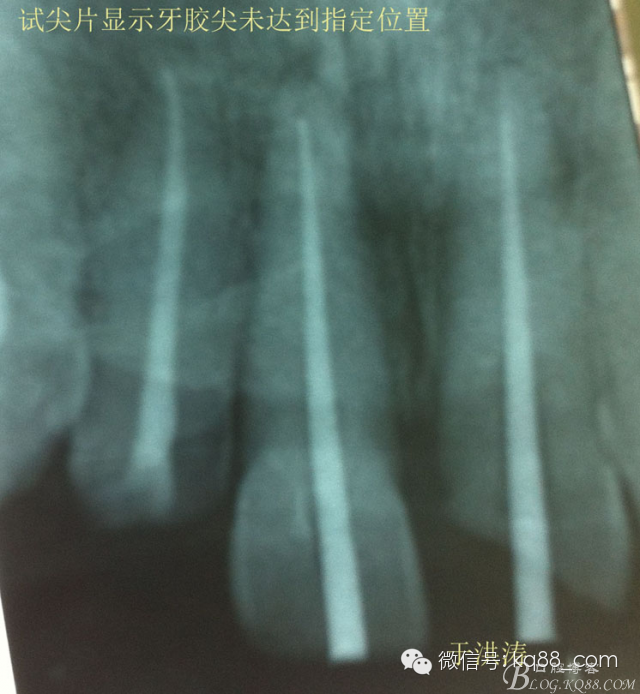

檢查:明顯可見22牙冠橫向斷裂至頸1/3處,近遠中與腭側斷裂至齦下??梢?/span>11牙冠斜向近中斷裂,近中與腭側均斷裂至齦下。21牙冠中1/3有裂痕。11 21 22松動(0),11 21叩(+),22叩(-),11 21 22探(-),11 21 22冷熱(-)。11 21 22唇側牙齦與粘膜和根尖相應部位未見明顯改變。11 22腭側牙齦增生性改變。11 21 22腭側粘膜和根尖相應部位未見改變。11 21 22舌側窩均有充填物。面部左右對稱無改變。余牙正常。(11,21,22牙冠顏色無改變)。 輔助檢查:X線片檢查11 22牙冠均有缺失。11 21 22 髓腔內均有充填物,11充填不到位, 21充填不實,22充填到位髓腔高密度影像。11 21 牙周膜有增寬,21根尖區(qū)有2mm左右低密度影像。未發(fā)現(xiàn)有牙根側穿或斷裂異物。 診斷:11,21慢性尖周炎,11,22殘冠。 治療計劃: 22無需治療。11 21 建議牙齒根管再治療。告知情況及費用。 1,11 21去除根充物。 2,11 21根管治療。 3,11 22纖維樁樹脂核修復。 4,高頻電刀去除11 22腭側牙齦組織到斷面。 5,11,21,22全瓷單冠修復牙齒。 治療過程:經(jīng)患者同意。H銼去除11 21原有充填物,未發(fā)現(xiàn)明顯滲出物,無異味。K銼疏通根管,VDW根測儀測量長度,11牙20mmWL,21牙20mmWL。S3鎳鈦器械預備根管。(全程1%次氯酸鈉沖洗EDTA溶解潤滑)試尖片顯示牙膠未到位,繼續(xù)向牙根尖各2mm進入預備。吸潮紙尖吸干根管,登士柏樹脂根充糊劑輸送至根尖部位,以測量數(shù)據(jù)用牙膠尖冷充側壓充填根管,3M玻璃離子封閉根管口。不可用患牙啃咬硬物,擇日冠修復。 輔助檢查:插針X線片顯示根管內充填物已經(jīng)取出。試尖片顯示牙膠尖未到位,繼續(xù)用K銼和機括向根尖預備。根充結束片顯示根充密實,無超充,無欠充。 醫(yī)囑:常規(guī)醫(yī)囑,不適隨診。 各步驟操作見下圖 于洪濤 2015.02.03 復 診 主訴:無疼痛,不適癥狀已經(jīng)消失。 檢查:11 21 充填物存在邊緣封閉完好,叩(-)松動(0)牙齦及周圍同初診。11 21 22無任何不適。 治療過程:由于患者自身原因即將兩個月來復診。拍X線片,去除11 22髓腔內部分牙膠,P鉆預備根管到達預定位置。粘結纖維樁,制作冠核。初預備11 21 22牙冠。高頻電刀按廠家要求功率和方法去除11 22腭側牙齦組織到達牙齒斷裂部位,調整檔位和功率繼續(xù)凝固和精修腭側組織,11 21 22排齦精修拋光。硅橡膠兩次法取模,可見模型完整肩臺清晰。制作臨時冠,科爾不含丁香油臨時冠粘結系統(tǒng)粘接。 模型送技師制作。預約義齒佩戴時間。(需術前牙齒比色) 輔助檢查:X線片顯示根尖低密度影像消失,牙周未見異常。X線片顯示纖維樁密合到位。 醫(yī)囑:不可用臨時牙肯咬硬物,不適隨診。 各步驟操作見下圖 于洪濤 2015.03.26 復 診 主訴:牙齒無癥狀,自感腭側術區(qū)舌舔粘膜不適。 檢查:臨時冠完整,無松動,邊緣緊密。牙齒無疼痛,唇側牙齦無明顯紅腫,腭側牙齦愈合良好,牙冠肩臺邊緣清晰。腭側牙齦術區(qū)中度觸及有少量滲血。 治療過程:義齒制作完成。去除臨時冠及粘結物。義齒試戴調整完全就位,無懸突,無縫隙。清洗義齒,氫氟酸處理義齒50秒(加強醫(yī)患防護),沖洗吹干,偶聯(lián)劑處理備用。基牙37%酸處理15秒,沖洗吹干,隔濕,排齦,涂第五代粘結劑。小蜜蜂雙固化樹脂水門汀激活攪拌注入義齒中,按順序就位,加壓力,牙線去除牙縫隙多余樹脂,涂阻氧劑,基牙唇腭側各光照固化3秒之后去除多余水門汀取出排齦線,繼續(xù)光照固化牙齒每個面20秒。精細查找去除多余水門汀。 醫(yī)囑:1,患牙咀嚼硬物加以注意。 2,常規(guī)醫(yī)囑,不適隨診,。 3,加強口腔衛(wèi)生意識。定期復診檢查。 各步驟操作見下圖 于洪濤 2015.04.07 回訪病例 主訴:咀嚼食物非常自如,無任何不適。 檢查:義齒牙體完整。無松動,無叩痛。唇側牙齦紅潤質韌無萎縮,腭側術區(qū)牙齦愈合良好,無炎癥改變。唇腭側根尖相應部組織無改變。余牙正常。 輔助檢查:X線片顯示牙根及周圍未見異常。未見骨萎縮。牙冠及頸部未見異常。 醫(yī)囑:定期檢查義齒,不適隨診。 各步驟操作見下圖 于洪濤2015.04.28